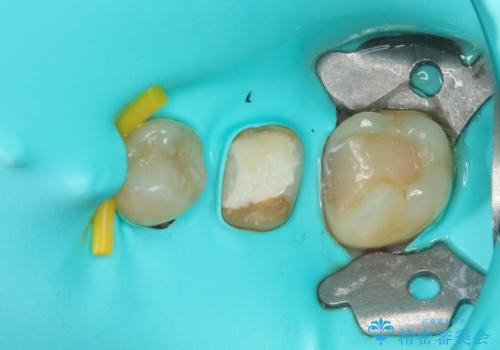

一番奥の歯は詰め物が脱離しており、仮詰め材が詰まっており、手前の歯は根管治療後に樹脂で固めたままの状態でした。

手前の歯を仮歯に置き換えるとともに、一番奥の歯のむし歯治療を行うこととしました。